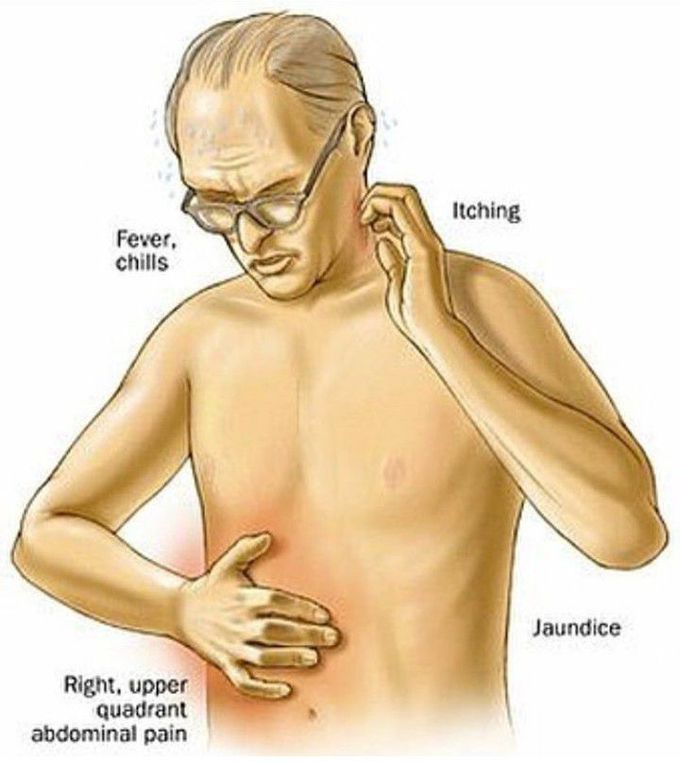

Изображения заболеваний печени: признаки и симптомы